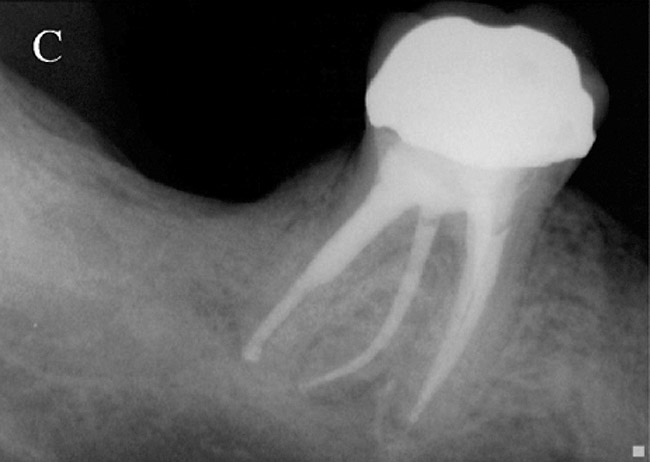

Figure 2a  Another case that clearly shows additional canal anatomy (distolingual root) not easily detected by periapical radiographs. Periapical radiograph depicting possible widened periodontal ligament (A). The CBCT clearly shows the missed canal in all three dimensions (B). The postoperative periapical radiograph shows the re-treatment, which includes the obturation of the distolingual canal24 (C).

Figure 2a

Figure 2c  Another case that clearly shows additional canal anatomy (distolingual root) not easily detected by periapical radiographs. Periapical radiograph depicting possible widened periodontal ligament (A). The CBCT clearly shows the missed canal in all three dimensions (B). The postoperative periapical radiograph shows the re-treatment, which includes the obturation of the distolingual canal24 (C).

Figure 2c

Initially, case studies appeared in the endodontic literature in which patients underwent CBCT imaging for the purposes of diagnosis20-22 and presurgical treatment planning.19 Recent reports have successfully shown the use of CBCT to locate missed canals,23 detect the extent of dentoalveolar fractures,20 identify resorption patterns,22 and compare cystic with granulomatous periapical lesions.17 Figure 2A through Figure 2C show a case in which the missed canal was suggested by periapical radiographs but confirmed with CBCT.24 Similarly in Figure 3A through Figure 3D, the additional diagnostic information attained from CBCT confirmed the diagnosis and extent of the root fracture, which initially was observed in the periapical radiographs (Figure 4A and Figure 4B).20 Notably, the extent of the lingual fracture as well as any alveolar complications could be visualized by CBCT only.